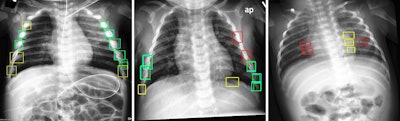

Test set images with ground truth (teal, red) and model predictions (green, yellow), with true positives (green), false positives (yellow), and false negatives (red). Predictions from the 6x-YOLOv5 ensemble trained on histogram equalized input images with a y = 0.2 avalanche scheme, achieving 0.536 precision, 0.795 recall, and 0.723 F2 score. Image and caption courtesy of Scientific Reports.

The model achieved an F2 score of 0.725, while expert interreader performance among seven board-certified pediatric radiologists with five to 20 years of experience yielded an F2 score of 0.732, according to the findings.